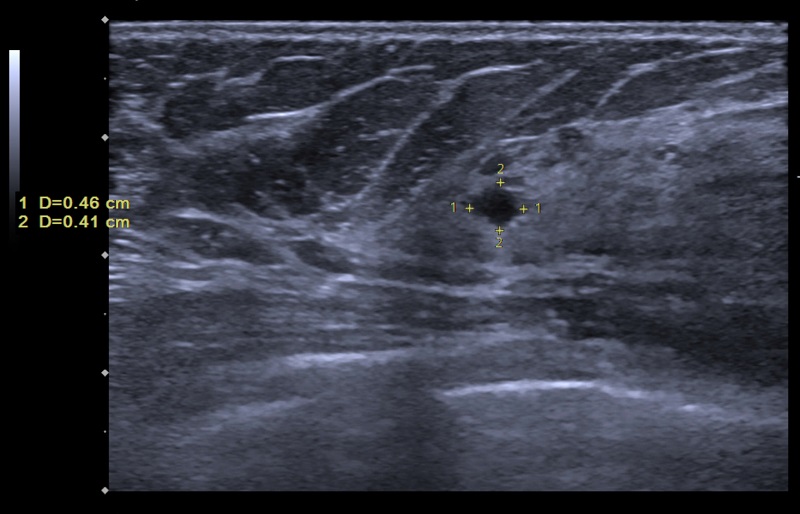

Hình ảnh siêu âm vú trên màn hình